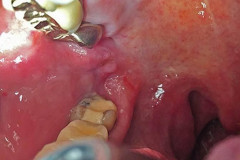

65-ամյա կնոջ լնդի միջից դուրս բերածը շոկի մեջ գցեց բժիշկներին (լուսանկարներ 16+)